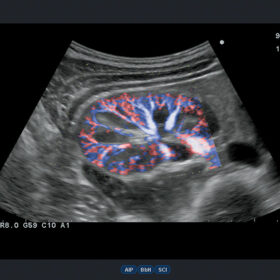

Ultrasound Aloka Prosound Alpha 6 – Image Gallery and Videos

- High blood flow definition: eFLOW

Incredible Imaging Technology Bringing About High Versatility

- eFLOW